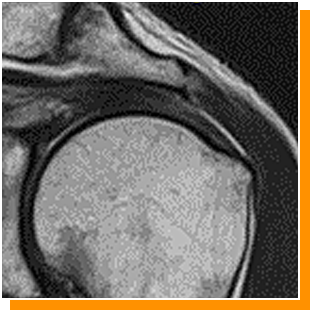

症例 3